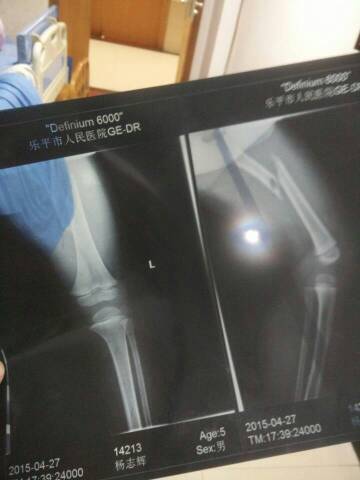

我孩子被车撞了,撞段了骨头,医生问我是打石膏,还是打钢钉,医生说打石膏可能有后遗症,打钢钉我怕孩子吃不消,我孩子今年3岁,那位医生帮我看一下,谢谢了,急急急急,这是片子。

孩子是股骨骨折,不好外固定。如果能对位国定好,不做手术也可以的。但是确实不好对位固定。我个人认为还是手术治疗恢复快一些。你可以咨询一下骨外科专家。